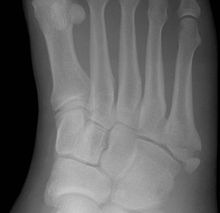

Cropped version of Jonesfracture.jpg

Jones fracture as seen on Xray

A Jones fracture is a break between the base and middle part of the fifth metatarsal of the foot.[8] It results in pain near the midportion of the foot on the outside.[2] There may also be bruising and difficulty walking.[3] Onset is generally sudden.[4]

The fracture typically occurs when the toes are pointed and the foot bends inwards.[6][2] This movement may occur when changing direction while the heel is off the ground such in dancing, tennis, or basketball.[9][10] Diagnosis is generally suspected based on symptoms and confirmed with X-rays.[3]

Diagnostic x-rays include anteroposterior, oblique, and lateral views and should be made with the foot in full flexion.